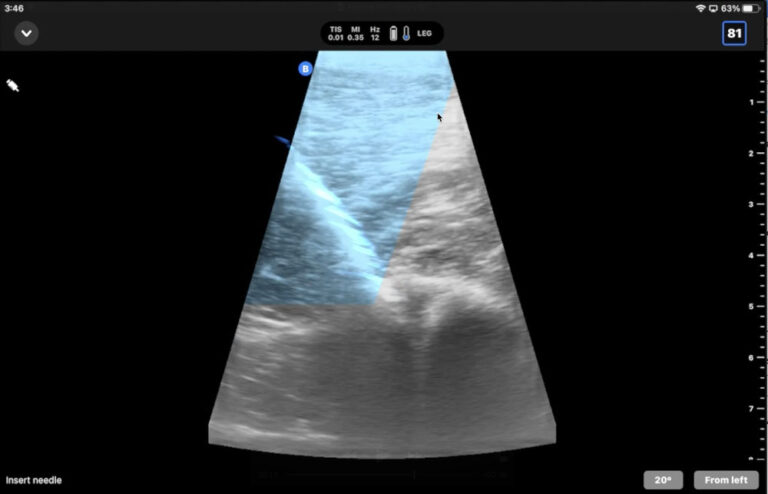

ultrasound-guided needle insertion Dr. Cooper Williams

Butterfly Ultrasound Tips: Ultrasound-Guided Injections